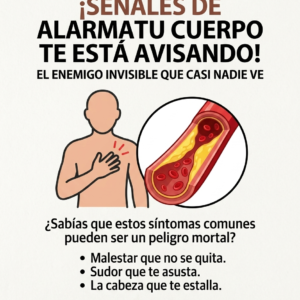

Cómo detectar posibles señales de colesterol alto antes de que afecte tu salud

El colesterol alto es “el enemigo silencioso” porque no causa dolor ni molestias al principio; va tapando tus arterias con grasa sin que te des cuenta. Cuando…